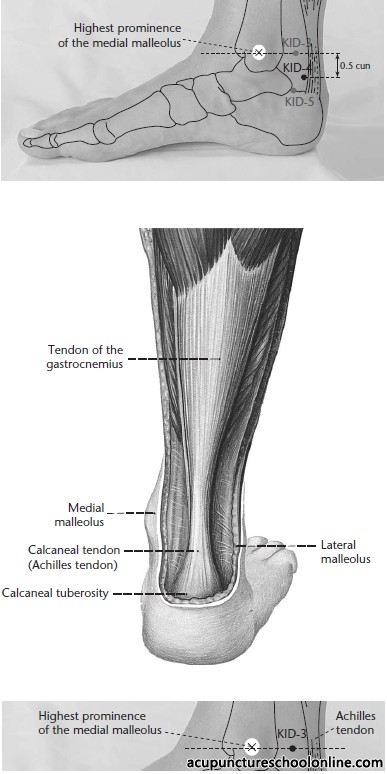

Approximately 0.5 cun posterior to the midpoint of the line drawn between Taixi Kid-3 and Shuiquan Kid-5, on the anterior border of the Achilles tendon

Superficial Innervation: Medial calcaneal branches of tibial nerve (S1 - S2)

Dermatome Segment: S1